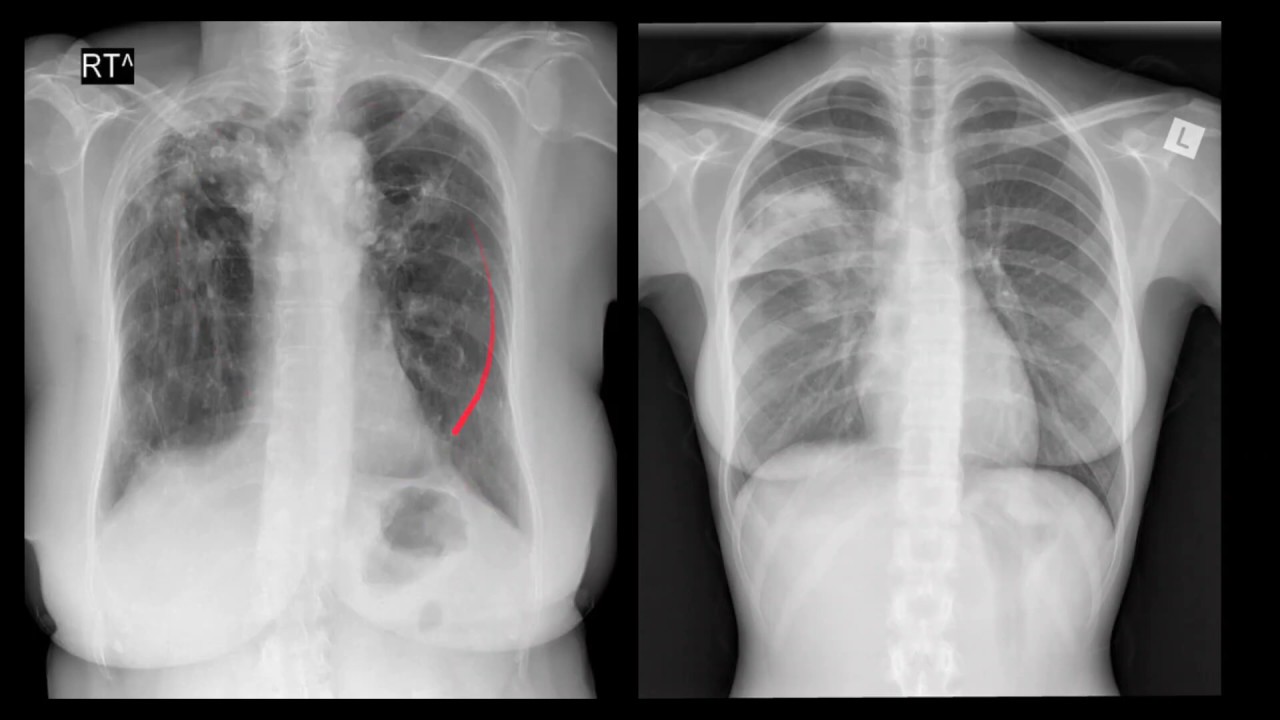

e dizer 'você sabe identificar tuberculose pulmonar tomografia não vão aprender junto aqui assistir com amigas e tomografia do tórax de um paciente com tosse crônica emagrecimento e sintomas constitucionais febre vespertina que a gente pode falar dessa tomografia aqui o paciente com tosse crônica emagrecimento a gente vai no nosso meio sempre considerar a possibilidade de tuberculose será que ele tenha achado os típicos de tuberculose na tomografia bom que a gente está vendo aqui quando a gente passa a gente vê vários nódulos olha só nódulos pequenos em todo o pulmão esses nódulos eles pegam tanto a região

centro lobo ao centro do logo quanto se você olhar com atenção eles pegam também as fissuras e até a região sub plural olha quanto nódulo tem nessa tomografia pegando praticamente todos os espaços no pulmão e não prefere nenhum é a distribuição chamada randômica uma distribuição como essa aqui com nódulos em todos os espaços pegando tantos entrou lá quanto o interstício ali interrogo la sobre o plural a fissura a gente vai colocar como primeira hipótese é uma doença com disseminação e matou gênica e adivinha qual é a disseminação da tuberculose me a isso mesmo e matou

gênica então fortalece a nossa hipótese de tuberculose mas minha agora será que é só isso bom se a gente olhar com calma não parece ser apenas o tipo de distribuição e matou jenny ou seja um nódulo com distribuição randômica que a gente vê nesse exame olha só essa sopa cidades aqui que feia essa capacidade mas se você olhar com atenção parece que ela tá arredondada fazendo um domo fazendo um halo só que um aluno que está mais disso do lado de fora e mais transparente menos denso do lado de dentro a gente chama isso de

halo invertido e quando a gente tenha invertido pode ter três padrões básicos o liso ou o último do dólar eo reticular esse aqui não poderia deixar de ser é o padrão multi novo lar olha o tanto de novo que tem na periferia e no interior dessa imagem alô invertido com base multimodulares é sinônimo de doença granulomatosa e adivinha quem é uma das principais doenças grão matosas no nosso meio tuberculose então mais um dado que fala a favor do beco lose agora o que é interessante é que além da disseminação e matou gênica esse paciente ainda

apresenta alguns nódulos sempre lobulares que parecem se ramificar olha só ele vem assim parecendo inscrever um vizinho para se inscrever um vizinho a gente encontra vários desses módulos no paradigma do paciente olha só como parece descrever um v tem outros têm inúmeros olha só como parece que ramifica esse aspecto é o fame gerado famoso aspecto de árvore em brotamento a então quando falharem brotamento é isso que dá querem dizer exatamente nós do centro lá e parece até que ramifica isso traduz uma doença que está com disseminação através das pequenas vias aéreas e tuberculose também faz

isso joão mais padrão de disseminação de vias aéreas junto com em matou gênio pode isso pode principalmente se o paciente foi mundo no deprimido ou seja se o paciente tem sida um exemplo é mais frequente da gente tivesse sobreposição de padrões então quais são os sinais de tuberculose que a gente vê nessa tomografia nódulos centro lobulares com distribuição randômica inferindo determinassem o agito o padrão dual invertido de base multimodulares que traduz doença granulomatosa eo padrão de árvore em brotamento novos centros populares com ramificação do tipo abrem brotamento que traduz um doença disseminada através de pequenas

vias aéreas cada um desses padrões está associado à tuberculose a presença dos três juntos fortalece muito a hipótese é claro eles sozinhos isolados não são específicos apesar de que no nosso meio se você vir deve sempre levantar essa hipótese visto que é muito prevalente tuberculose todas as suas apresentações no nosso meio ok valeu e até a próxima